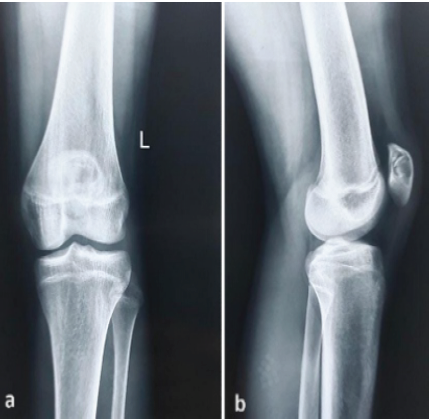

Postoperatively, the patient was immobilized in an extension knee brace for 4 weeks, after which functional rehabilitation exercises were initiated. At 6-month follow-up, there was no clinical or radiological evidence of recurrence (Fig. 4), and the patient had returned to his sporting activities without pain.

Figure 4: Six-month post-operative radiograph demonstrating graft incorporation within the patellar defect.